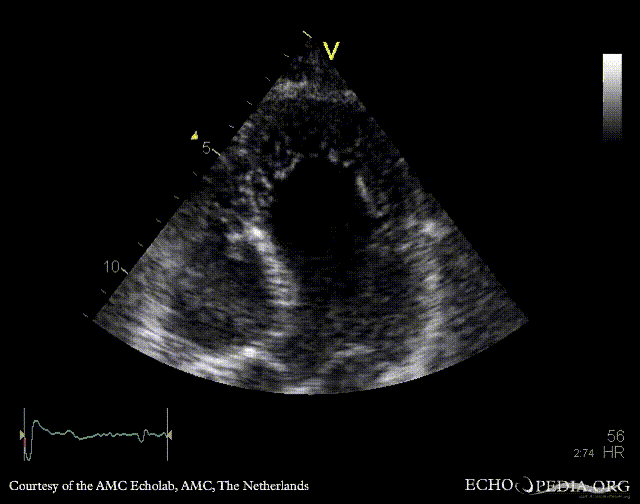

Case 112